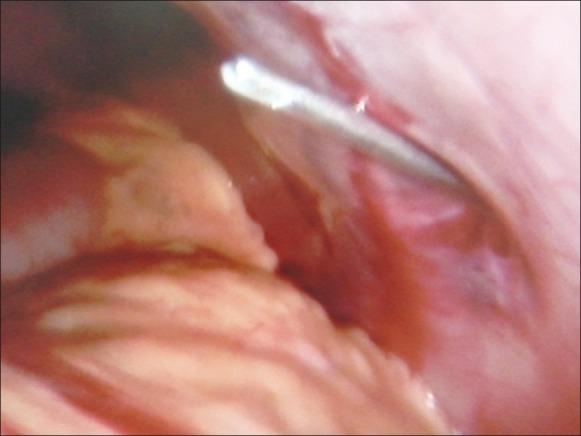

经左下腹肋间隙插入Veress针建立气腹:75例经验

Veress needle insertion through left lower intercostal space for creating pneumoperitoneum: Experience with 75 cases.

The aim of this study has been to evaluate the safety and efficacy of lower left intercostal space (LICS) for VNI.

In part one, skin fold thickness (SFT) was measured in 32 patients at SUF, LICS, right iliac fossa (RIF) and Palmer's point. As part two, in these patients, VNI was carried out from LICS under laparoscopic guidance. As part three, same technique of VNI was employed in 43 patients with suspected intra-abdominal adhesions undergoing laparoscopy for various reasons. Observations were made regarding ease of insertion, attempts needed for successful entry, loudness or clarity of give-way feeling of Veress needle, intra-abdominal bleeding at point of emergence of Veress needle, hemopneumothorax, bowel or vascular injury.

SFT at LICS was significantly less as compared to SUF and Palmer's point. VNI at LICS was easy to carry out; it could be successfully done in first attempt in all patients, and was associated with very clear and loud give-way feeling. There were no instances of intra-abdominal bleeding at point of emergence of Veress needle, hemopneumothorax, bowel or vascular injury.

VNI at LICS as described here is safe and effective.